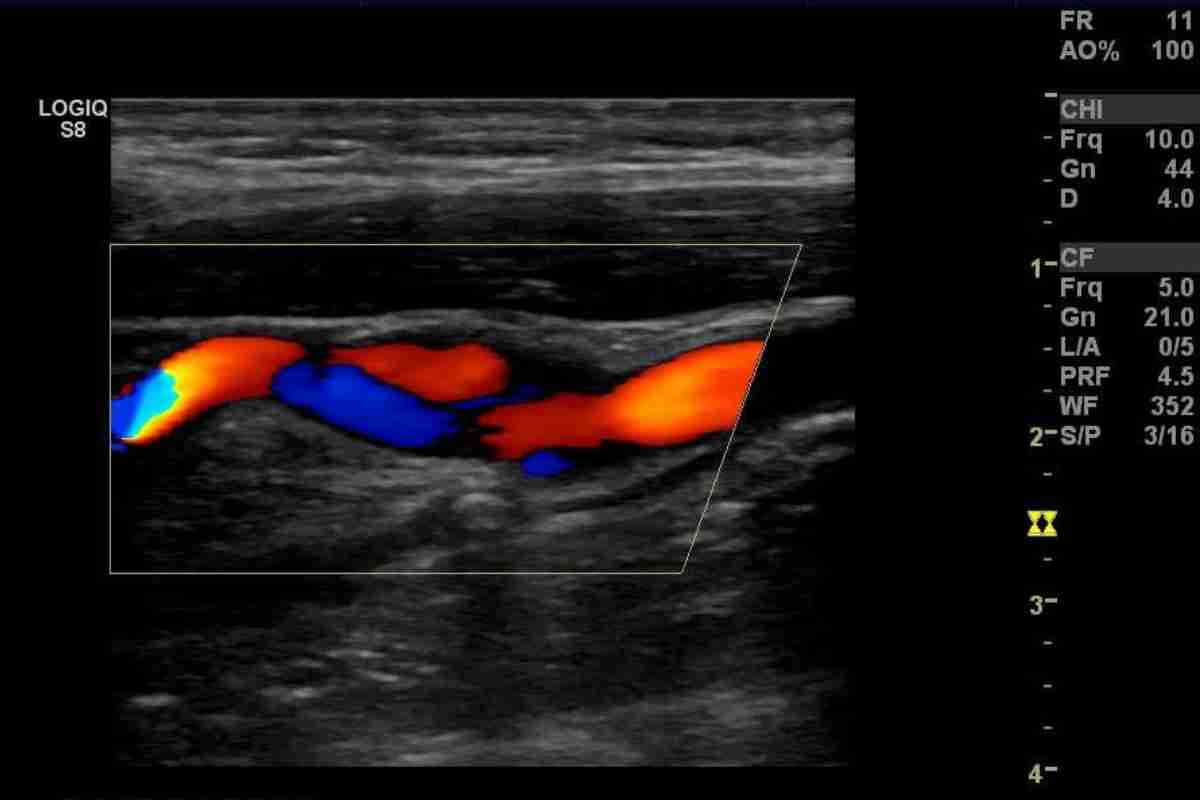

Assess blood flow in arteries and veins, helping to diagnose conditions such as deep vein thrombosis (DVT) or carotid artery disease.